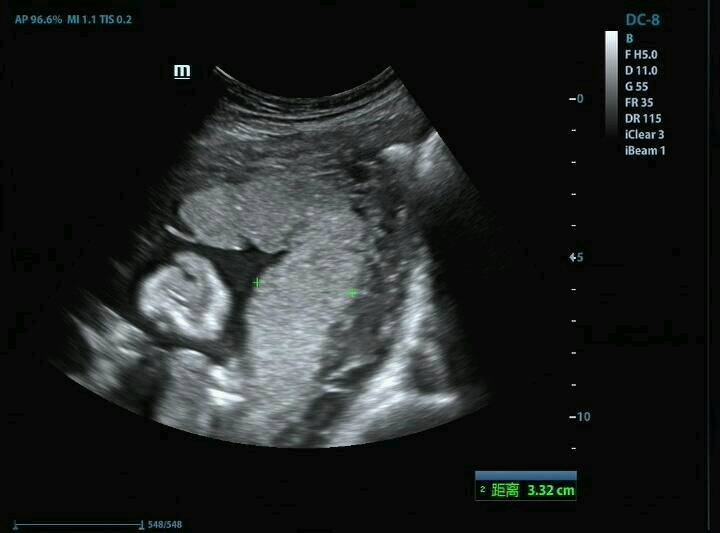

大家帮忙看看这张四维彩超能看出宝宝性别吗?刚拍的,好好奇呀! 点击展开 匿名用户 2014-10-31 16:33 为您推荐: 其他回答 你好,根据图片不能判断是男是女,只能通过B超动态观察胎儿性别。孕期保持良好情绪。孩子发育的就错不了。 张笑珠 2014-10-31 18:02 相关问题 看四维彩超结果辨男女准吗?我对肚子里的宝宝性别很好奇,想做个B超检查一下 有经验的宝妈帮忙看看,怀孕8个多月啦!好好奇宝宝的性别呢 第一次当妈妈,很好奇肚子里的宝宝性别,有经验的妈妈帮忙看看,32周了 好激动